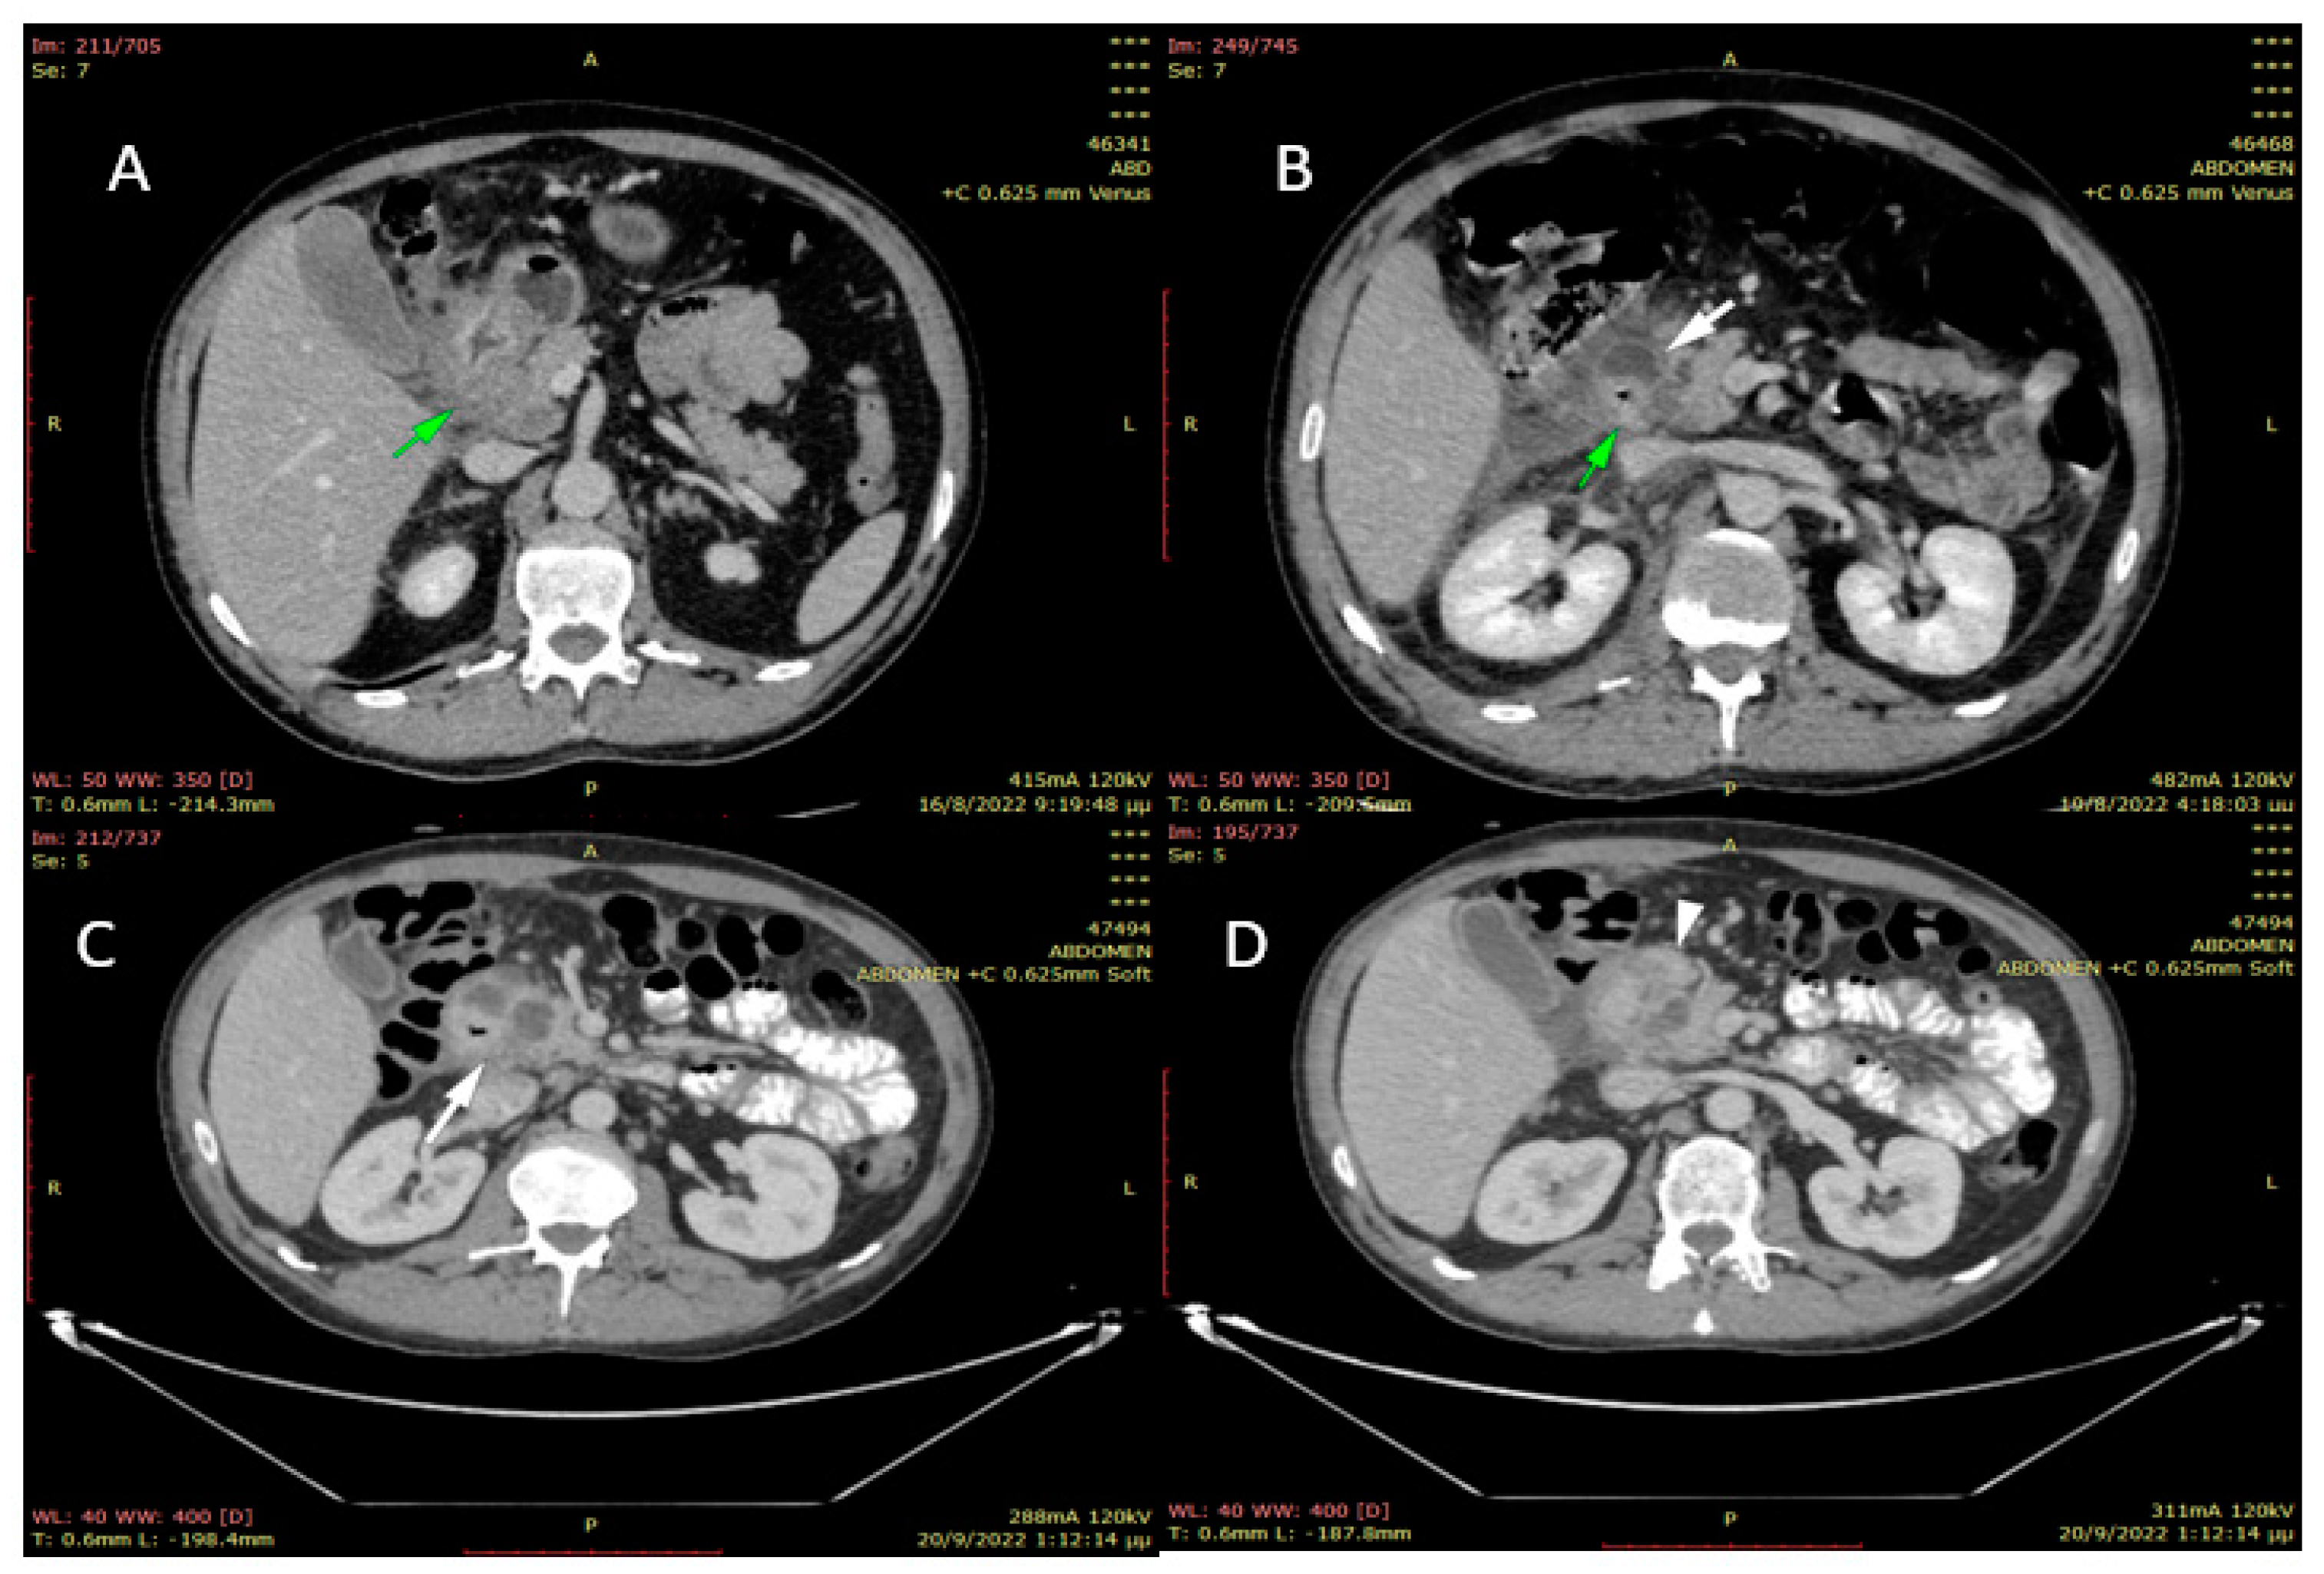

2. Case Presentation